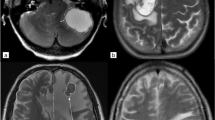

This study aims to investigate the predictive value of preoperative whole-tumor histogram analysis of multi-parametric MRI for histological subtypes in patients with lung cancer brain metastases (BMs) and explore the correlation between histogram parameters and Ki-67 proliferation index. The preoperative MRI data of 95 lung cancer BM lesions obtained from 73 patients (42 men and 31 women) were retrospectively analyzed. Multi-parametric MRI histogram was used to distinguish small-cell lung cancer (SCLC) from non-small cell lung cancer (NSCLC), and adenocarcinoma (AC) from squamous cell carcinoma (SCC), respectively. The T1-weighted contrast-enhanced (T1C) and apparent diffusion coefficient (ADC) histogram parameters of the volumes of interest (VOIs) in all BMs lesions were extracted using FireVoxel software. The following histogram parameters were obtained: maximum, minimum, mean, standard deviation (SD), variance, coefficient of variation (CV), skewness, kurtosis, entropy, and 1st–99th percentiles. Then investigated their relationship with the Ki-67 proliferation index. The skewness-T1C, kurtosis-T1C, minimum-ADC, mean-ADC, CV-ADC and 1st – 90th ADC percentiles were significantly different between the SCLC and NSCLC groups (all p < 0.05). When the 10th-ADC percentile was 668, the sensitivity, specificity, and accuracy (90.80%, 76.70% and 86.32%, respectively) for distinguishing SCLC from NSCLC reached their maximum values, with an AUC of 0.895 (0.824 – 0.966). Mean-T1C, CV-T1C, skewness-T1C, 1st – 50th T1C percentiles, maximum-ADC, SD-ADC, variance-ADC and 75th – 99th ADC percentiles were significantly different between the AC and SCC groups (all p < 0.05). When the CV-T1C percentiles was 3.13, the sensitivity, specificity and accuracy (75.00%, 75.60% and 75.38%, respectively) for distinguishing AC and SCC reached their maximum values, with an AUC of 0.829 (0.728–0.929). The 5th-ADC and 10th-ADC percentiles were strongly correlated with the Ki-67 proliferation index in BMs. Multi-parametric MRI histogram parameters can be used to identify the histological subtypes of lung cancer BMs and predict the Ki-67 proliferation index.